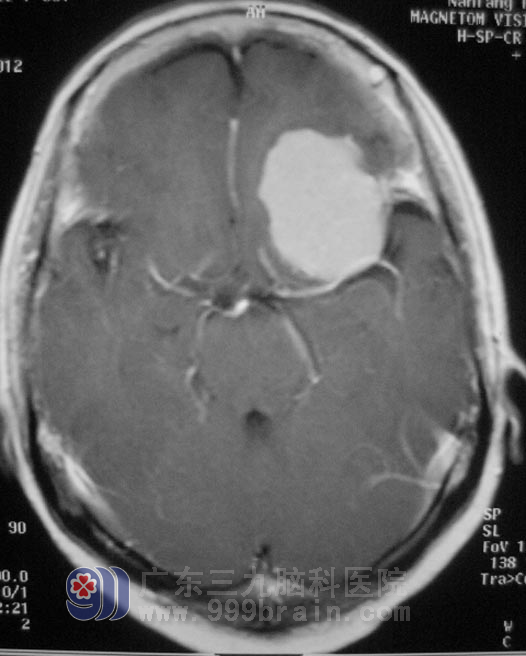

偏偏在半个月前,李女士又出现了间歇性头晕;一周前,头晕症状加重,伴有头痛。当地医院行头颅MR检查提示左侧蝶骨嵴占位性病变,考虑脑膜瘤。真是祸不单行。

在广东三九脑科医院住院后,经过全面检查及评估,李女士各项功能均可接受手术治疗。2月1日,由综合神经外科 鲁明主任主刀,在全麻下行左侧蝶骨嵴脑膜瘤切除术+颅内压探头植入术,术中见颅骨及硬膜血供丰富,肿瘤呈粉红色,质硬,包膜完整,广基与蝶骨嵴中外1/3硬膜相连,在显微镜下分块全切肿瘤,手术过程顺利。手术后没有出现并发症,已康复办理出院。术后病理结果为:合体型脑膜瘤。